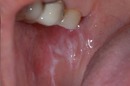

口の中のどこにできる?(舌・頬・歯茎など)

頬の内側:もっとも一般的。

舌の横や裏:白斑が見られやすいです。

歯茎や唇の裏:発生することもあり、視認しづらいため注意が必要。

口蓋(上顎内側):稀に見られる部位。

口の中に白っぽい「線状・網目状・斑点状」の病変が現れ、粘膜が硬く、時に痛みやヒリヒリ感、赤みを伴います。病変部がむずがゆい、物を噛むときに不快感がある、口内炎が繰り返すような感覚が現れる方も多いです。